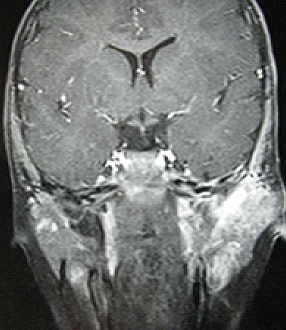

Le sarcome d'Ewing est une tumeur osseuse agressive, rapidement évolutive et métastatique. La localisation pétreuse est rare. Elle présente des difficultés diagnostiques et thérapeutiques. La prise en charge doit être multidisciplinaire. Le meilleur traitement reste chirurgical au prix de séquelles fonctionnelles et esthétiques. L'avènement de nouvelles molécules de chimiothérapie a amélioré le pronostic. Garçon âgé de 16 mois, sans antécédentsparticuliers a présenté une otorragie spontanée gauche. L'examen physique a révélé une formation charnue, saignante, non battante, comblant le conduit auditif externe gauche. Le patient n'avait pas de paralysie faciale ni d'adénopathies cervicales palpables. La TDM des rochersa révélé un processus tissulaire du conduit auditif externe gauche, étendu à l'oreille moyenne avec lyse du mur de la logette et de l'os temporal. L'IRM des rochers a montré le même processus avec envahissement de la parotide gauche, en hyposignal T1, se réhaussant après injection de gadolinium. L'examen anatomo-pathologique d'une biopsie osseuse a confirmé le diagnostic d'un sarcome d'Ewing. Le bilan d'extension n'a pas retrouvé de métastases. La chimiothérapie d'induction (6 cures de Vincristine, Ifosfamide, Doxorubicine et Etoposide) a permis une réduction tumorale de plus que 80%. Une intervention chirurgicale a consisté en une pétrectomie gauche, parotidectomie exo-faciale conservatrice et un curage triangulaire. L'examen histologique a confirmé un sarcome d'Ewing avec des limites de résection saines. Une chimiothérapie post-opératoire de 6 cures de VAI (Vincristine, Actinomycine, Ifosfamide) a été instaurée. Une rémission clinique et radiologique était notée avec un recul d'un an.